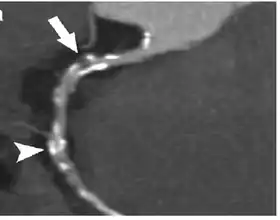

Coronary Computed Tomography Angiography (CCTA)

Computed tomography angiography (CTA), an imaging methodology using a ring-shaped machine with an X-ray source spinning around the circular path so as to bathe the inner circle with a uniform and known X-ray density. Cardiology uses are growing with the incredible developments in CT technology. Currently, multidetector CT, specially the 64 detector-CT are allowing to make cardiac studies in just a few seconds (less than 10 seconds, depending on the equipment and protocol used). These images are reconstructed using algorithms and software.

A coronary CT calcium scan is a computed tomography (CT) scan of the heart for the assessment of severity of coronary artery disease. Specifically, it looks for calcium deposits in the coronary arteries that can narrow arteries and increase the risk of heart attack.[17] This severity can be presented as Agatston score or Coronary Artery Calcium (CAC) score. The CAC score is an independent marker of risk for cardiac events, cardiac mortality, and all-cause mortality.[18] In addition, it provides additional prognostic information to other cardiovascular risk markers.[18] A typical coronary CT calcium scan is done without the use of radiocontrast dye, but it can possibly be done from contrast-enhanced images as well, such as in coronary CT angiography.[19]